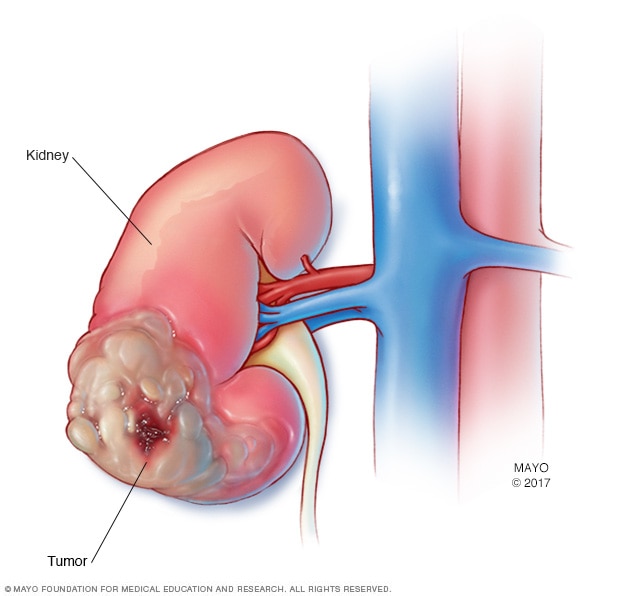

Kidney cancer

Kidney cancer is a growth of cells that starts in the kidneys.

Kidney cancer is a growth of cells that starts in the kidneys. The kidneys are two bean-shaped organs, each about the size of a fist. They're located behind the abdominal organs, with one kidney on each side of the spine.

Kidney cancer happens when cells in the kidney develop changes in their DNA. A cell's DNA holds the instructions that tell the cell what to do. In healthy cells, the DNA gives instructions to grow and multiply at a set rate. The instructions tell the cells to die at a set time. In cancer cells, the DNA changes give different instructions. The changes tell the cancer cells to make many more cells quickly. Cancer cells can keep living when healthy cells would die. This causes too many cells.

The cancer cells form a mass called a tumor. The tumor can grow to invade and destroy healthy body tissue. In time, cancer cells can break away and spread to other parts of the body. When cancer spreads, it's called metastatic cancer.